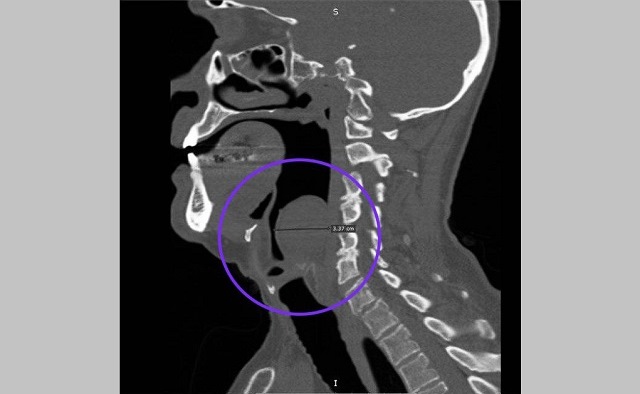

Гигантскую миксому гортани удалили 67-летнему пациенту оториноларингологи Республиканской клинической больницы (РКБ).

Медики отметили, что опухоль из соединительных тканей выросла у татарстанца уже во второй раз. Впервые образование выросло до 3 см в диаметре еще в 2021 году.

В этот раз медики удалили образование диаметром 8 см. Операция длилась около полутора часа. Дополнительные разрезы не потребовались — все сделали через рот. Сейчас мужчина уже идет на поправку.

По словам врачей, обычно миксомы вырастают в сердце. Подобное образование в горле — редкость. В России было описано всего два подобных случая.